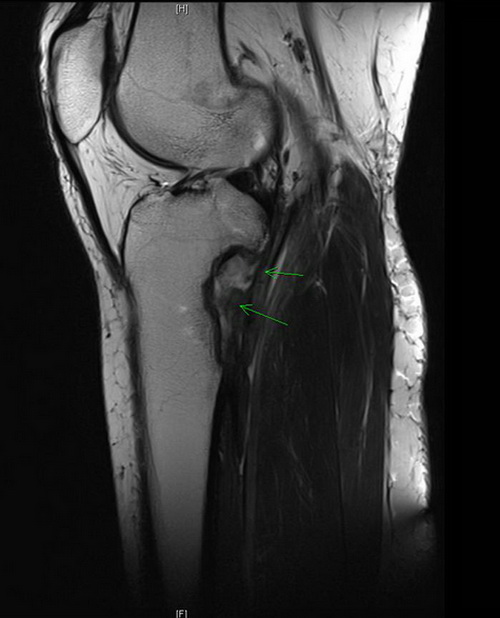

MRT

Sag T2 tse 512 p2

Die Verlaufskontrolle via MRT des Kniegelenks links sollte im ersten Jahr in dreimonatigen Abständen erfolgen. Die Lunge soll mittes Röntgen-Thorax a.p. ebenfalls in 3 monatigen Abständen nachkontrolliert werden.